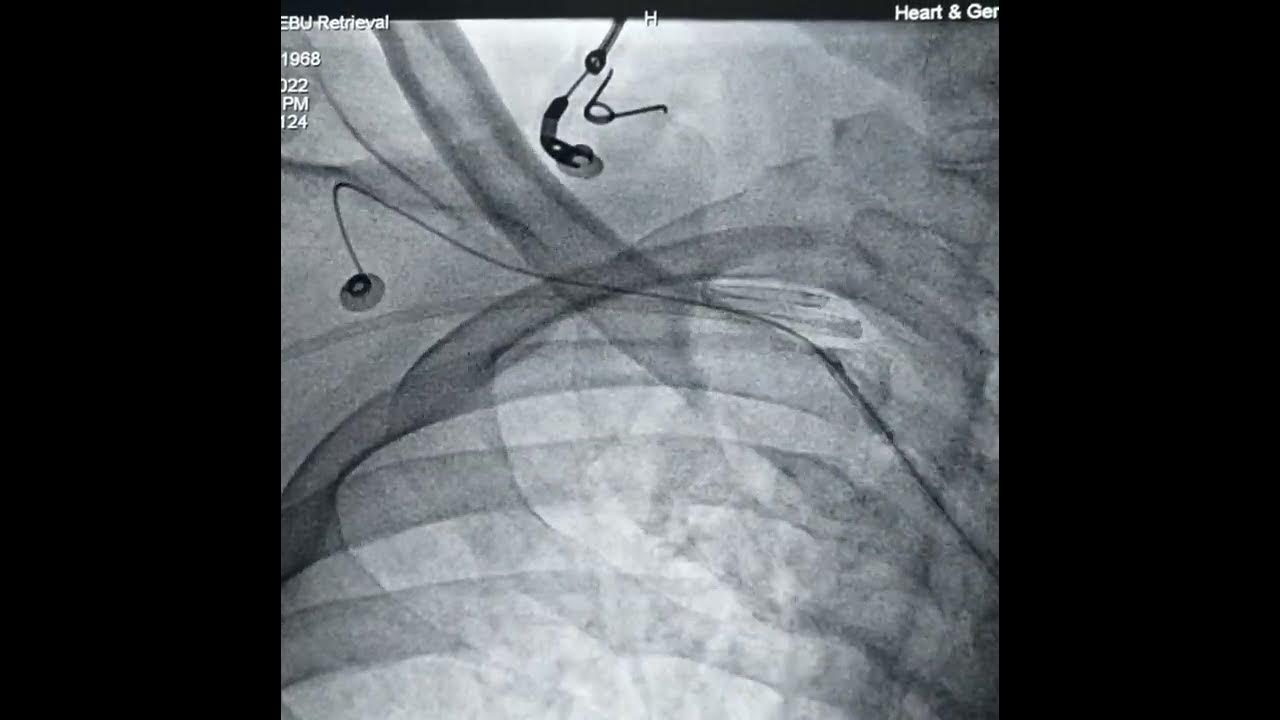

Guiding catheter (EBU) entrapped in right subclavian artery YouTube Guide Catheter Manipulation Guiding catheters can be divided into active or passive manipulation types. A universal catheter is meant to cannulate multiple vessels in a single use, whereas most femoral catheters are meant for a single,. Guide catheters for coronary intervention. Choosing the proper guide catheter size and shape can help ease the transition to radial adoption. Guide catheter support is key to. Guide Catheter Manipulation.